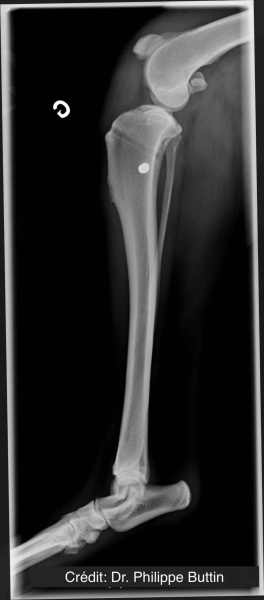

Radiologické snímky